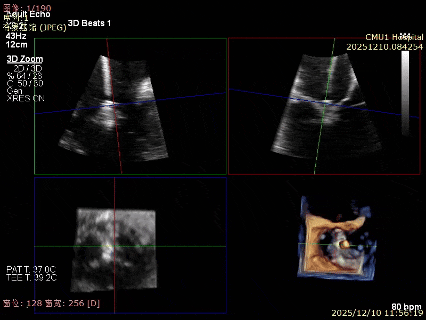

为了避免长时间TEE对食道造成损伤,术前即刻3D-TEE短时进一步明确二尖瓣病变相关解剖情况。

术前3D

3D-TEE二尖瓣相关解剖学参数:后叶长度:22-25mm,前叶长度:31-34mm;瓣环AP径:47mm,ML径:48mm;瓣口面积:约7.8cm²;脱垂宽度:30mm,最大连枷间距:14mm。

四条肺静脉均可测及收缩期反向血流

术前即刻TEE进一步明确了二尖瓣反流的机制(DMR)及反流程度(5+),重点完善了病变区域二尖瓣解剖结构的评估,预估手术难点/影响手术效果的解剖结构为冗长的二尖瓣后叶(PML约25mm),宽大的脱垂(Flail Width约30mm),超大的连枷间距(Flail gap约14mm)。